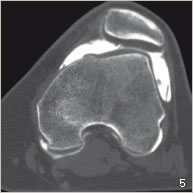

Une rétraction de l’aileron externe associée à une insertion trop latéralisée du tendon rotulien et de la tubérosité tibiale antérieure sur le tibia provoquent une bascule externe de la rotule voire un véritable déplacement de celle-ci sur le côté responsable d’un défaut de contact des surfaces articulaires (figures 2 et 5). Ceci peut occasionner une gêne à type de douleurs, de blocages, de gonflements, ou d’instabilité avec de véritables luxations de la rotule.